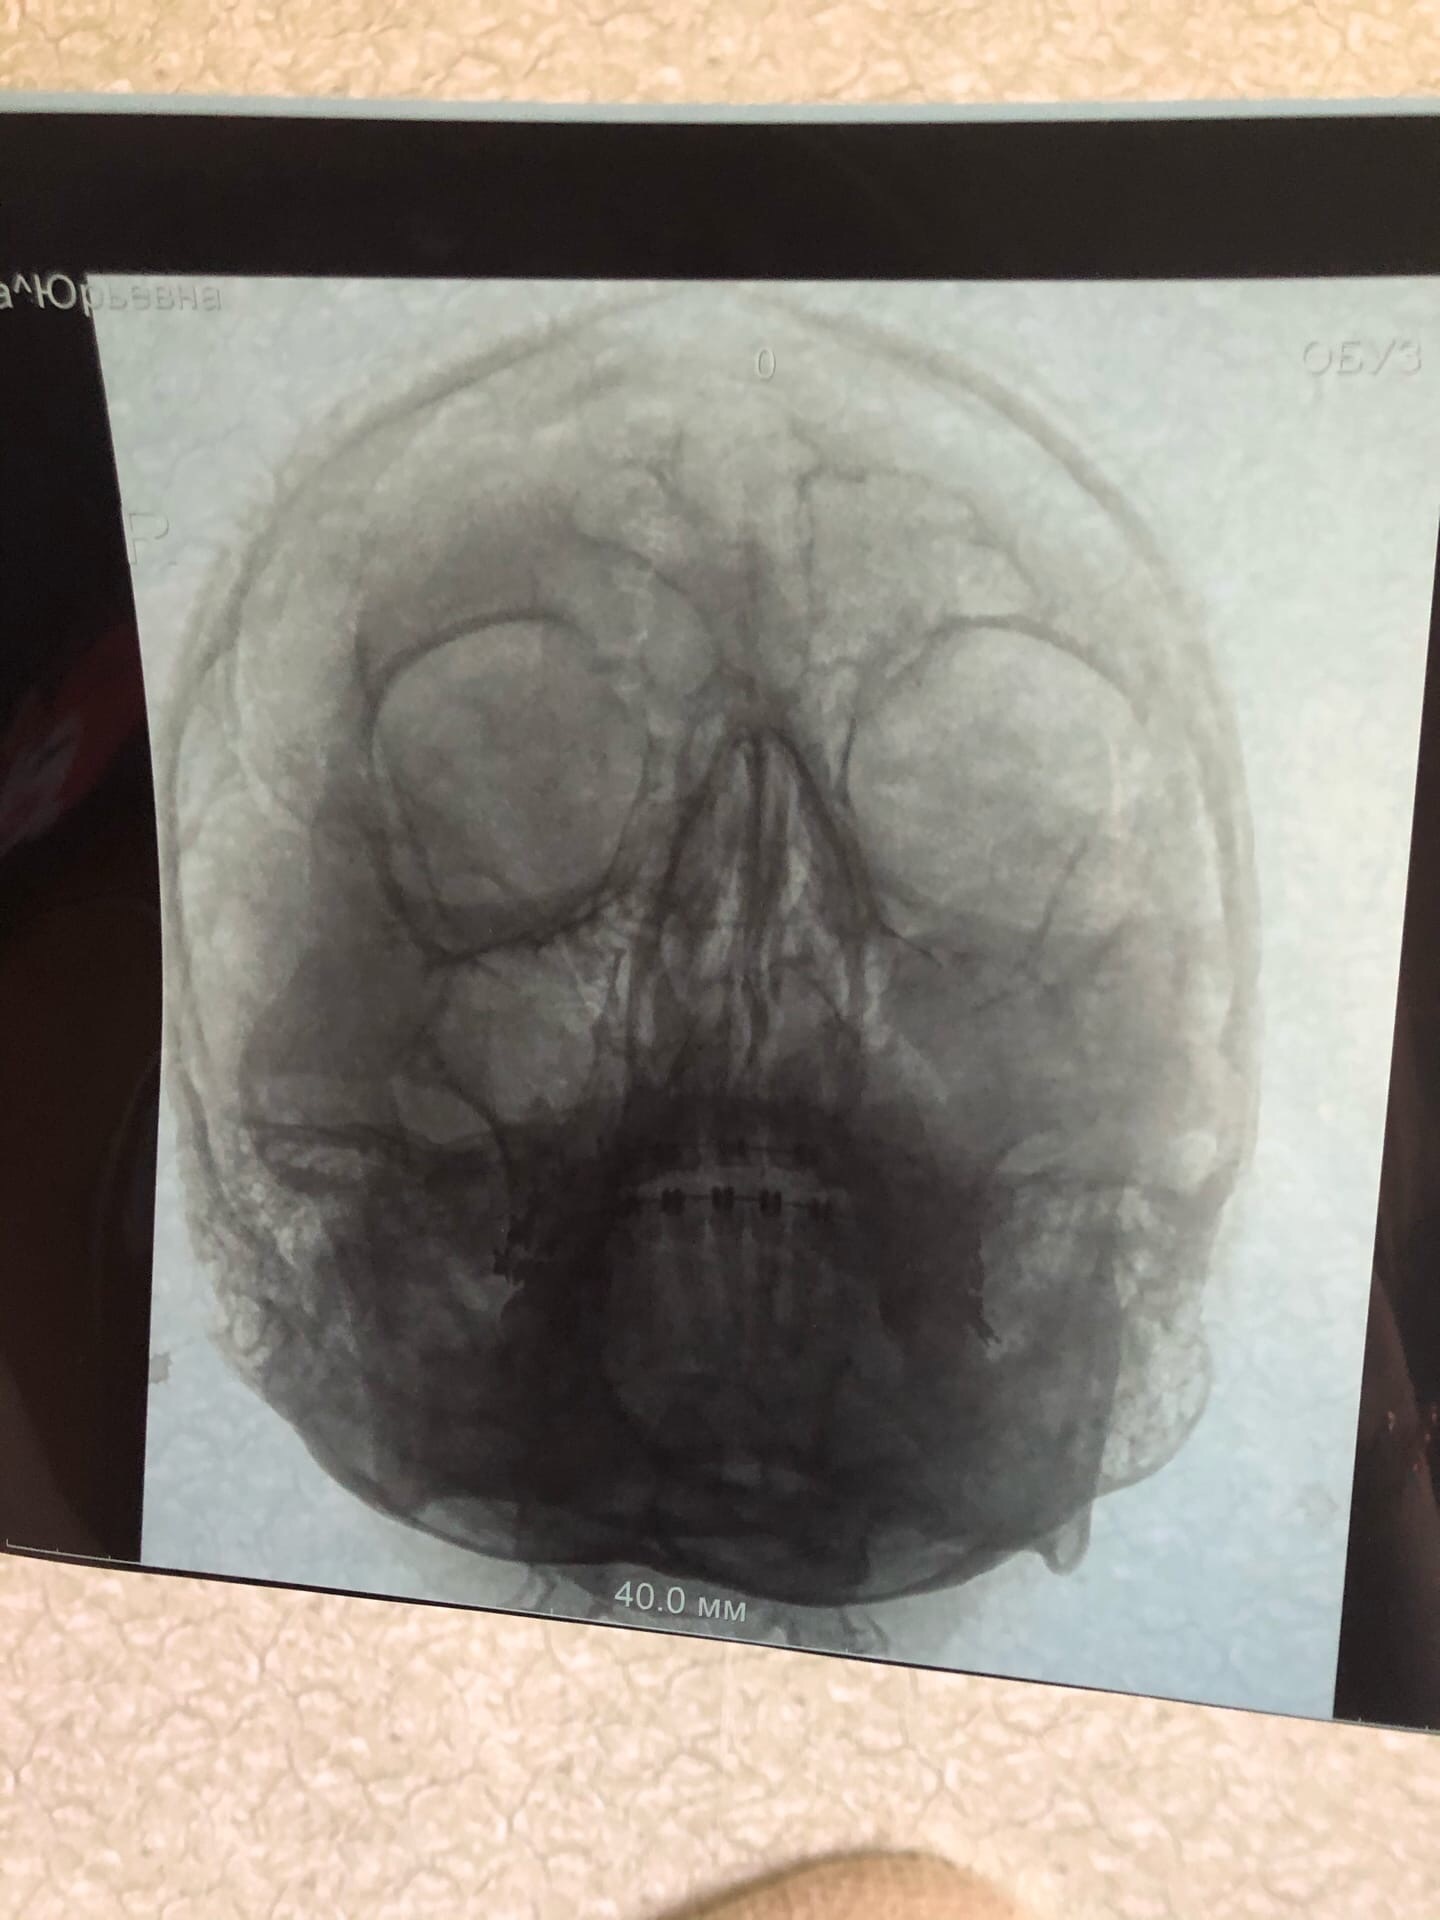

Затемнение во лбу

Ребята, помогите понять что это? Был гайморит, вроде как вылечила, остался только отёк. Сделала контрольный снимок, показывает затемнение во лбу. Но если бы это бил фронтит затемнена же была бы тогда полностью лобная пазуха, а не какая-то часть на пересечении? ЛОР сказал, что это строение моего черепа, но как сомнительно верится